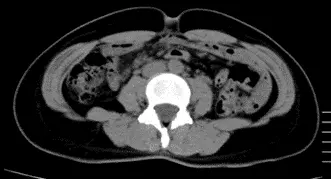

AFTER

OurAge×Webエクラ AFTER-2

体重 75.0kg   −2.0kg

腹囲 101.0cm   −2.0cm

体脂肪の量

全体 457.23㎠    −18.14㎠

内臓脂肪 177.80㎠ −14.45㎠

皮下脂肪 279.43㎠ −3.69㎠

「Cさんは、3週間〈齋藤式満腹やせメソッド〉を実践する前に、すでに1カ月間、食事にMCTオイルを取り入れていたそうで、その時点で体重が1.5kg落ちたようです。ですからもともとの体重は78.5kgで、その後〈齋藤式満腹やせメソッド〉を実践して75kgまで落ちているので、体重は3.5kg落ちたということ。

しかも、〈齋藤式満腹やせメソッド〉をそこまで厳密に行ったわけでなく、とにかく、MCTオイルを食事に足すようにしたそう。それだけでも、3週間で内臓脂肪は14.45㎠、皮下脂肪は3.69㎠も減少したので、MCTオイルの効果の高さがわかりますね。CT検査の画像でも内臓脂肪が落ちていることがよくわかります。また、〈齋藤式満腹やせメソッド〉実践前は中性脂肪値が214mg/dlと基準値以上だったのですが、実践後は126mg/dlと正常値になったのもすばらしい変化。続けることで、さらに効果が表れると思います」